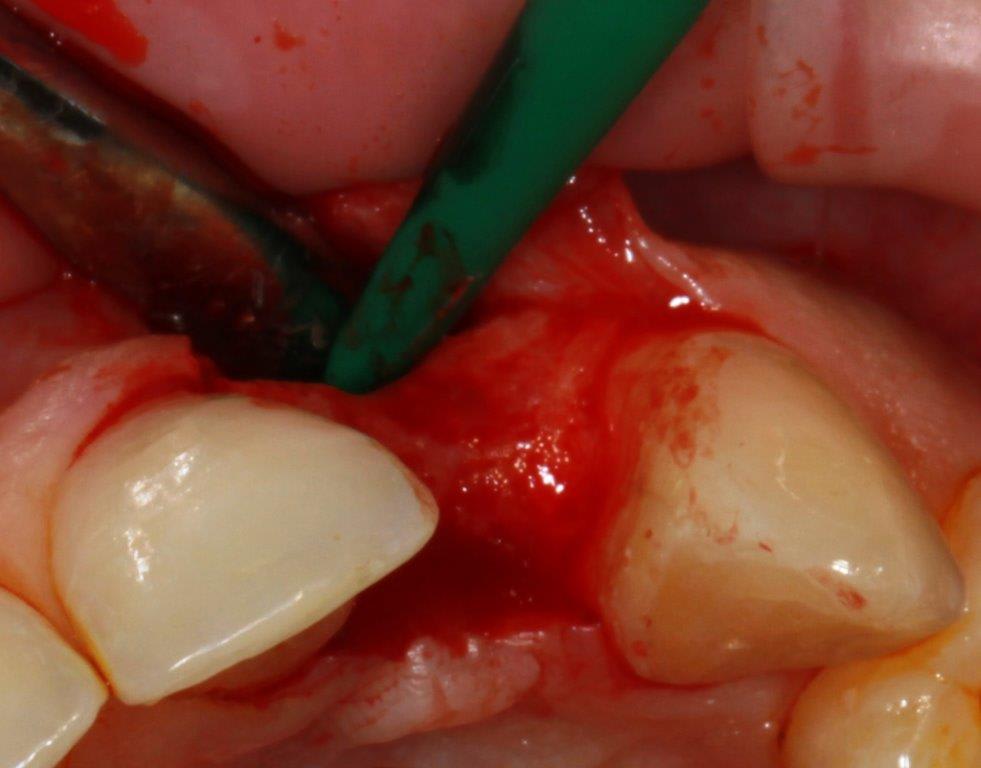

pour ceux que ça intéressent, une petite utilisation d'expansion de la paroi palatine, sur une avulsion d’incisive(racine fendue). toutes mes excuses pour la mauvaise qualité des photos.